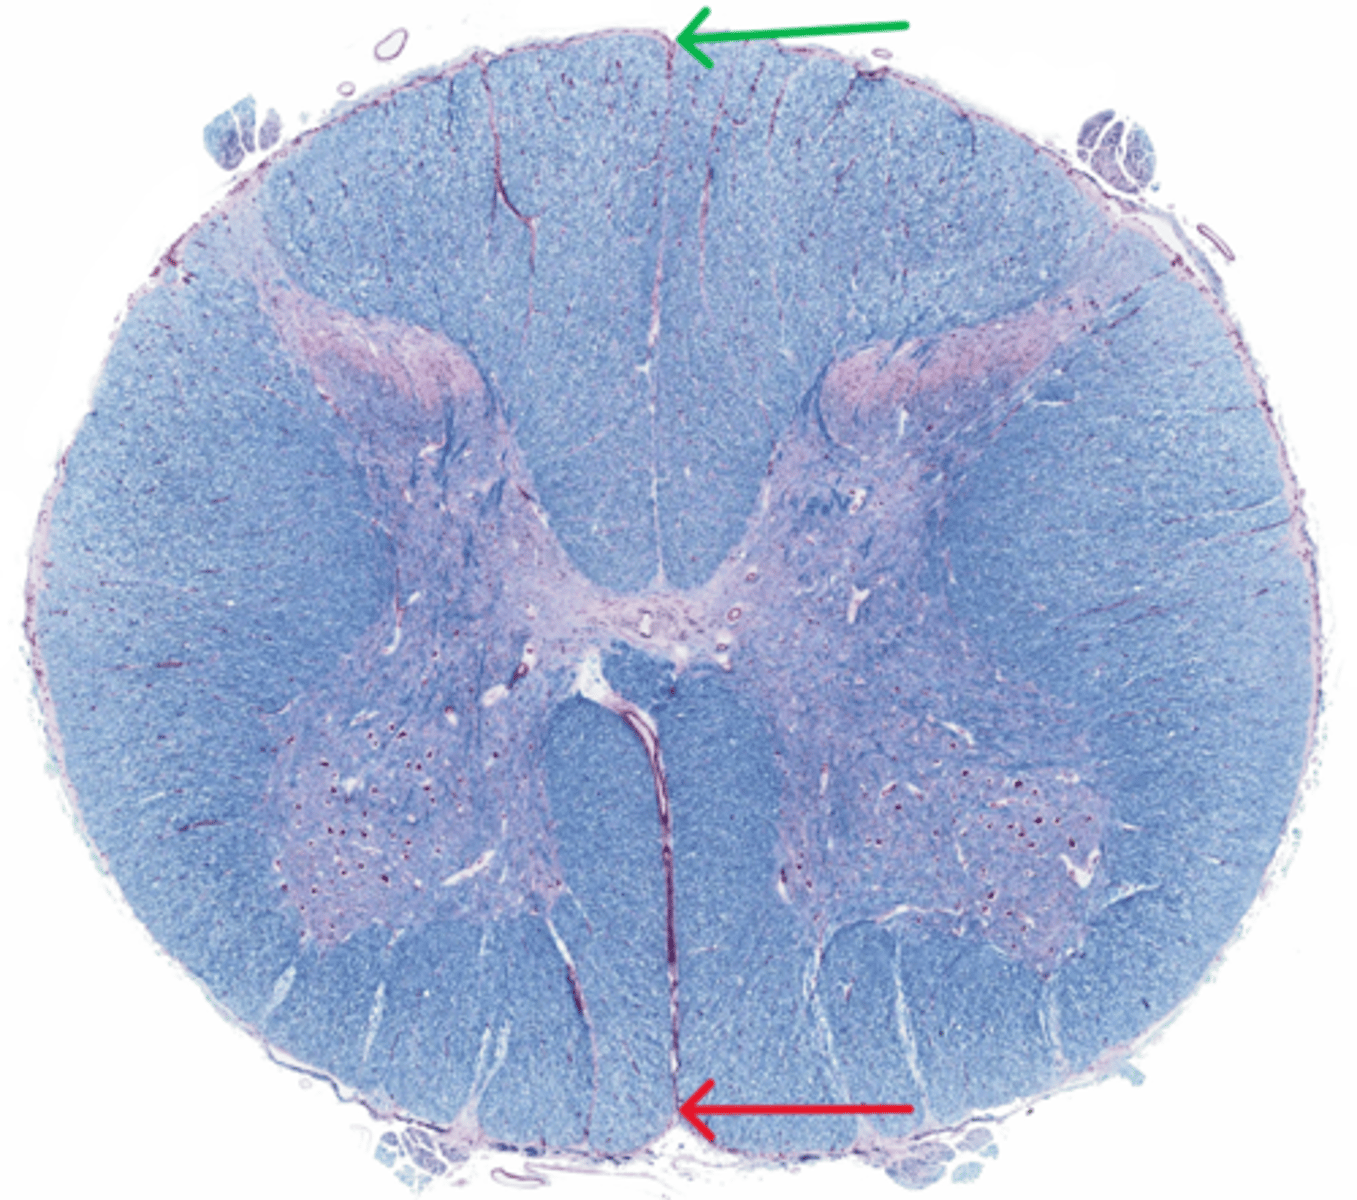

Posterior median sulcus

green

Anterior median fissure

red